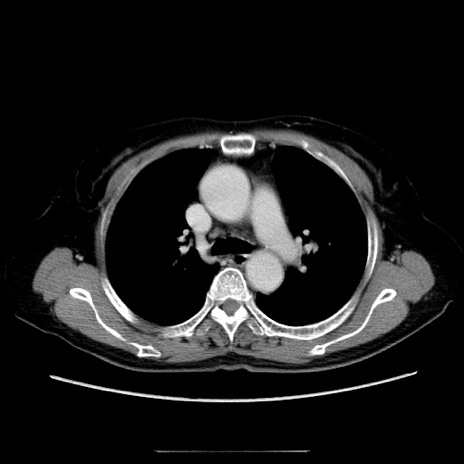

冠状断像

【症例】70歳代女性

【主訴】お腹が張る

【現病歴】1週間くらい前から腹部膨満の自覚あり。昨日夜から増悪したため、本日救急外来受診。

【身体所見】意識清明、BT 36.5℃、BP 165/106mmHg、HR 80bpm、SpO2 98%、腹部:膨満、軟、自発痛・圧痛なし、触診にて不快感あり、腸蠕動音:減弱

【データ】WBC 12600、CRP 1.04